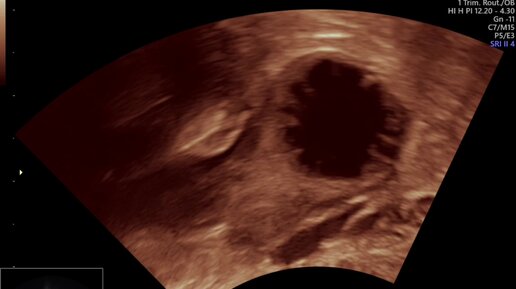

Овуляция – это выход готовой к оплодотворению яйцеклетки (ооцита) из фолликула яичника.